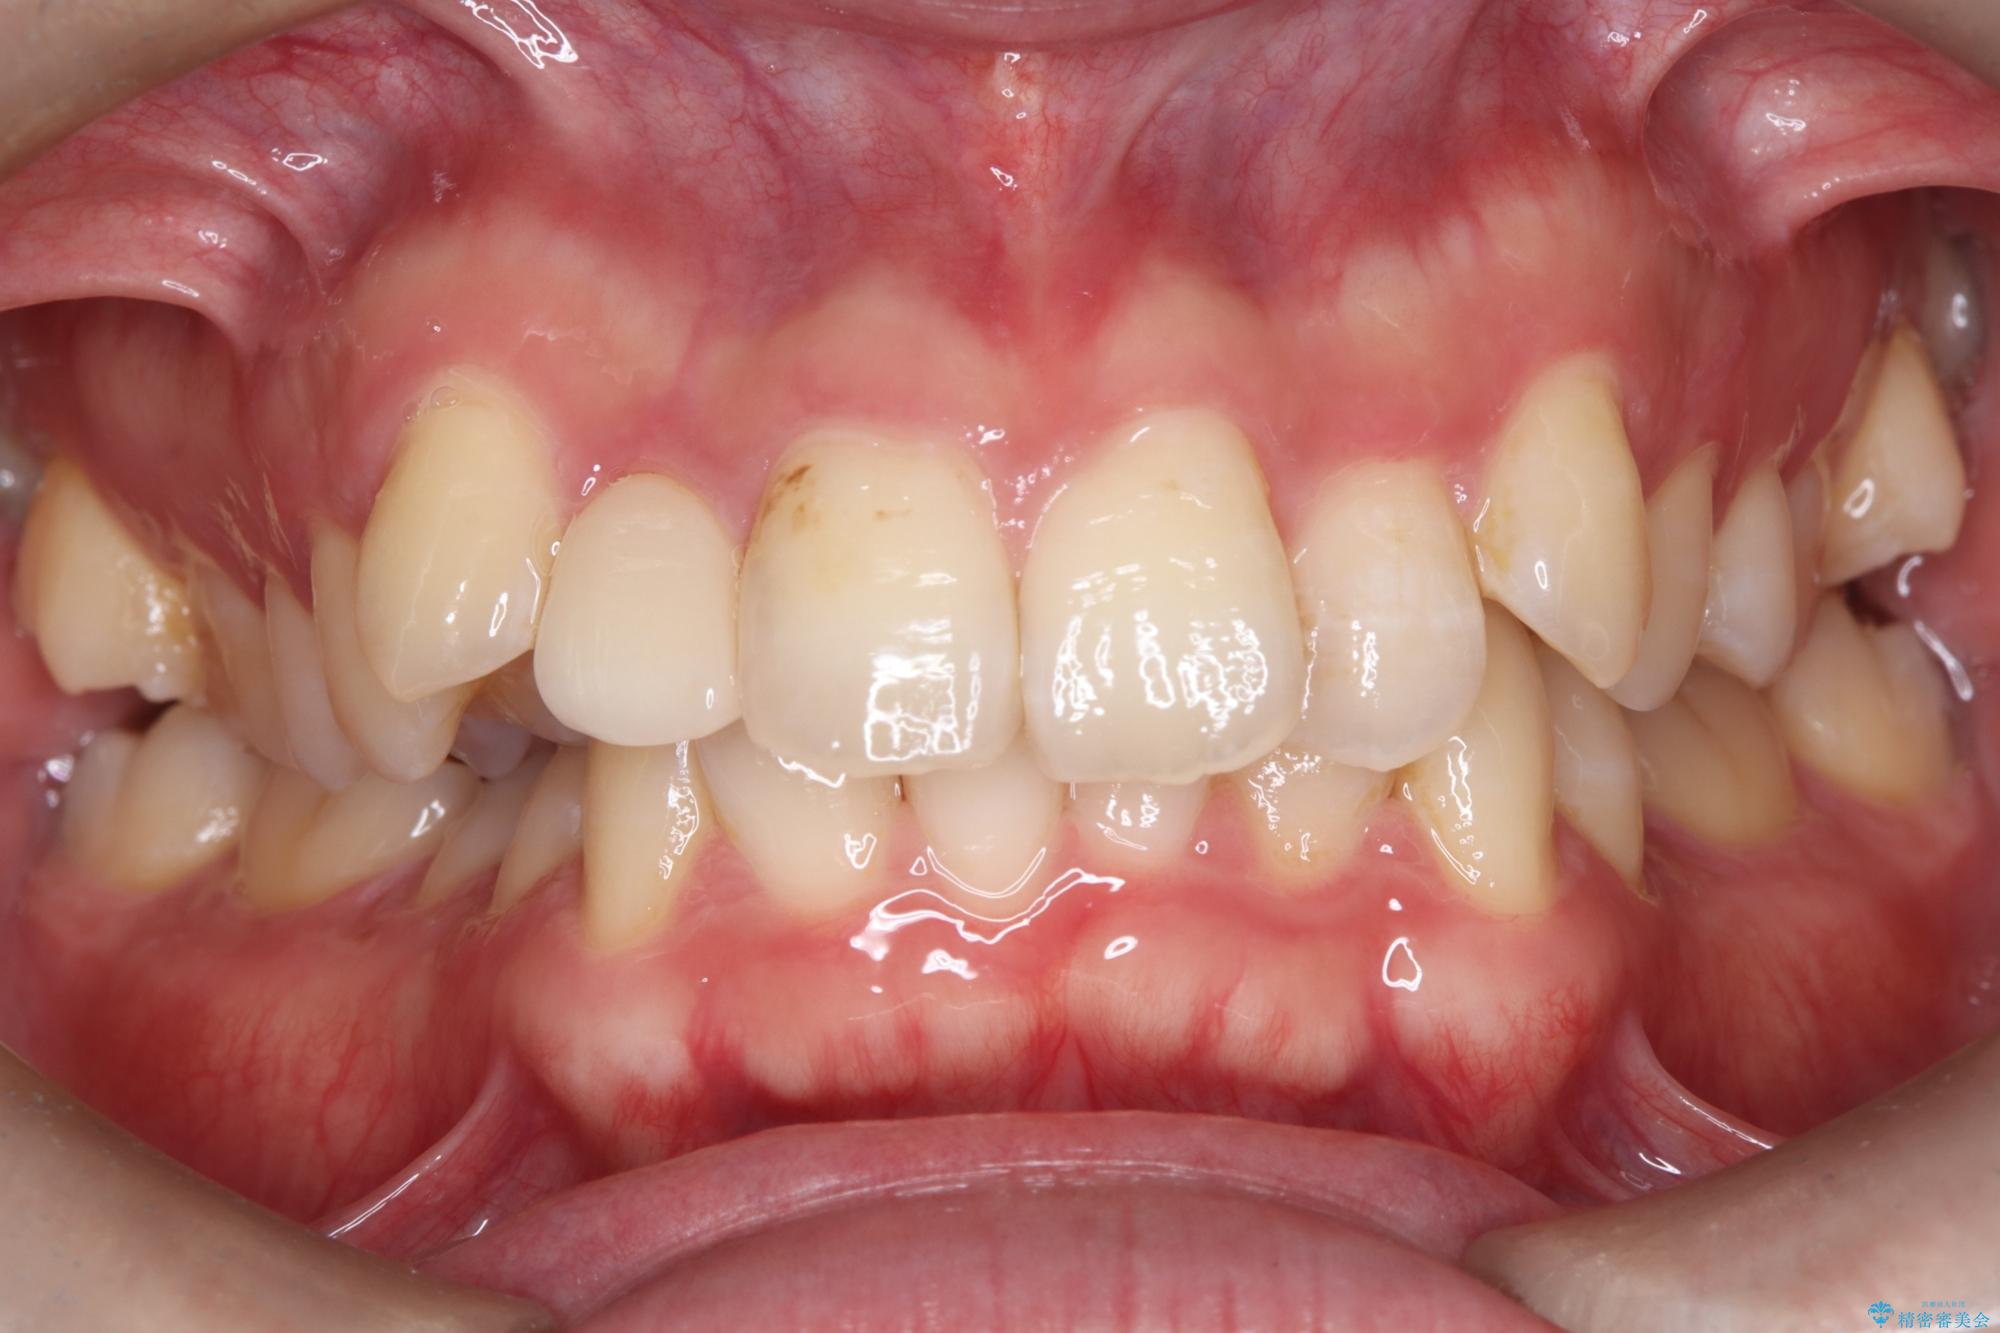

- 主訴:右上の前歯が何しなくても痛い

右上2番の歯に自発痛を認め、症状や歯髄診・レントゲン像から不可逆性歯髄炎と診断し、精密根管治療から歯冠補綴まで行うこととなりました。

初診時に歯髄診断を行い、不可逆性歯髄炎と診断し抜髄から補綴修復までの流れを説明し、精密根管治療、ファイバ-コア築造、オールセラミッククラウン(St)修復を行うこととしました。